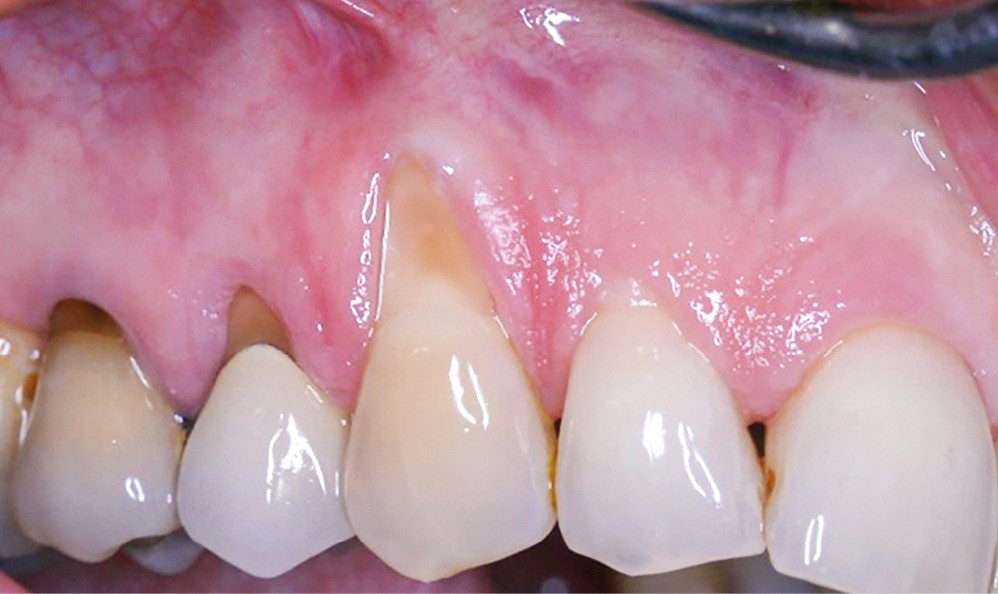

La greffe épithélio-conjonctive (GEC) [7, 8] consiste au remplacement du tissu parodontal existant par un greffon épithélio-conjonctif dont l’indication principale est l’augmentation en hauteur et en épaisseur du tissu kératinisé (fig. 2). Elle peut aussi être utilisée dans le recouvrement radiculaire (avec des résultats en termes de recouvrement inférieurs à ceux des techniques de greffe de conjonctif enfouie), l’aménagement des crêtes édentées, l’aménagement péri-implantaires [9, 10] (fig. 3), ou en association avec un traitement ortho-parodontal [11]. Le principal défaut de cette technique est son aspect inesthétique ; elle sera donc réservée à des zones non visibles comme les incisives mandibulaires ou les zones postérieures.